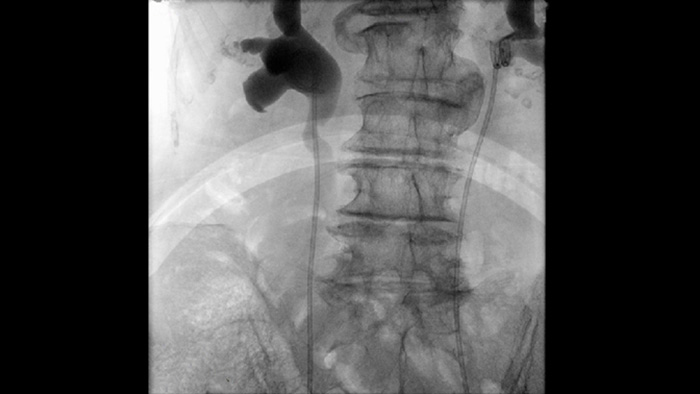

Strategien zur Senkung der Strahlungsbelastung für Patienten und Anwendern bei interventionellen Verfahren stehen gegenwärtig im Mittelpunkt des wissenschaftlichen Diskurses. Unsere Zenition mobilen Lösungen für die Chirurgie basieren auf dem Philips DoseWise Zenition Konzept – eine spezielle Kombination von Techniken, Programmen und Verfahren für ein effizientes Dosismanagement. Diese Kombination liefert bei interventionellen Verfahren in der Gastroenterologie und der Urologie mit effizientem Strahlendosismanagement für Patienten und Anwender die erforderliche klinische Bildqualität.

Die gepulste Durchleuchtung verbessert die Bildgebung bei dichtem Gewebe und komplexen Strukturen und unterstützt Sie beim Management der Strahlendosis. Es stehen verschiedene Durchleuchtungspulsfrequenzen zur Auswahl, um nach Bedarf die Dosis zu reduzieren oder die Bildqualität zu erhöhen.

Vorgegebene Bildgebungsparameter für verschiedene Verfahren und Anatomien, die für jede Anwendung individuell angepasst werden können, steigern die klinische Sicherheit und Effizienz, ganz gleich, wie unterschiedlich Ihre Verfahren und Patienten sind.